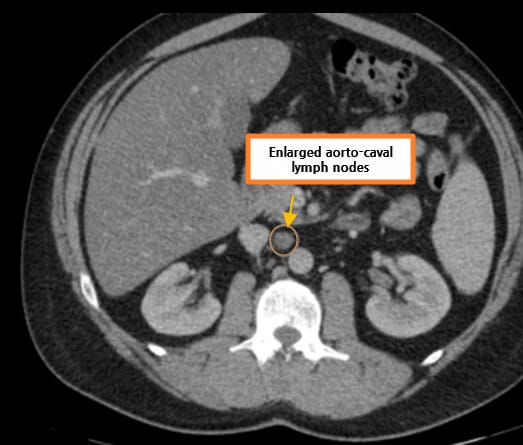

영상소견 정리

CT/ MRI 소견

조영증강 영상에서 고형성 종괴 + 중심 괴사, 혈관 침범

| CT/ MRI 소견 |

| ✅ 신정맥, 하대정맥 침범 |

| 정맥 내 종양 혈전이 관찰되며, 이는 병기와 치료 방침에 결정적 영향을 미칩니다. |

| ✅ 폐 또는 뼈 전이 |

| 흉부 CT에서 다발성 폐 결절, 골스캔에서 골 전이 소견이 있을 수 있습니다. |

Renal cell carcinoma 병기

신세포암(Renal cell carcinoma, RCC)의 병기는 종양의 크기와 신장을 넘는 침범 정도, 림프절 전이 여부, 원격 전이 여부에 따라 TNM Staging 체계로 분류합니다. 병기는 예후 예측과 치료 결정에 매우 중요합니다.

| Stage III (T3 또는 N1, M0) |

| 종양이 신장을 넘어 신정맥, 대정맥 또는 주변 지방조직에 침범하거나 림프절 전이가 있으나 원격 전이는 없음. |